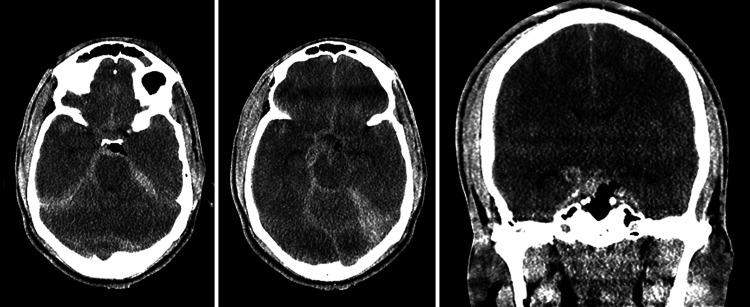

OBSERVATIONS

The clinical course of a patient who sustained an injury to the right posterior communicating artery followed by infarction due to vasospasm after severe traumatic brain injury is presented, along with a focused literature review.

本文介绍了一名患者的临床病程,该患者在严重创伤性脑损伤后右侧后交通动脉受伤,随后因血管痉挛发生梗死,并进行了重点文献综述。